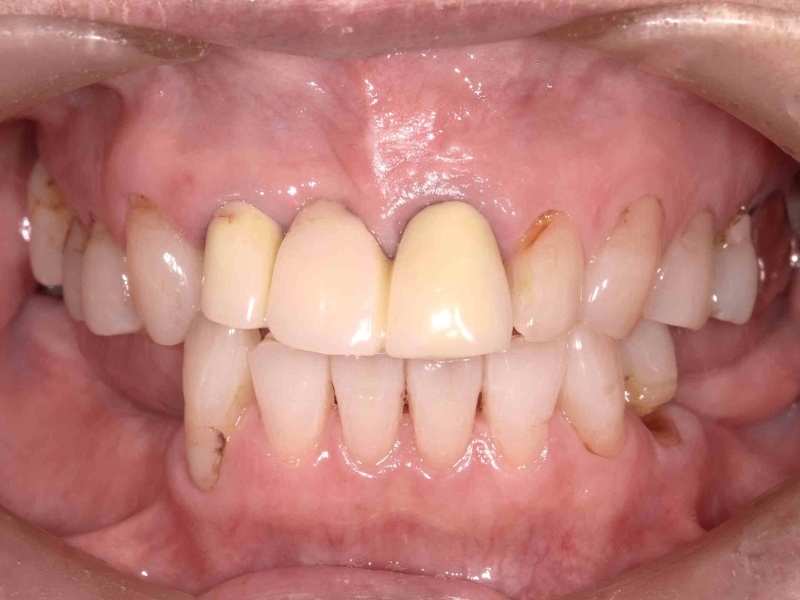

<症例2>60歳代 男性

長年放置したために歯周病が進行し噛みにくくなった患者様が、インプラントを入れ全顎的な治療を行い、審美改善しました。

正面